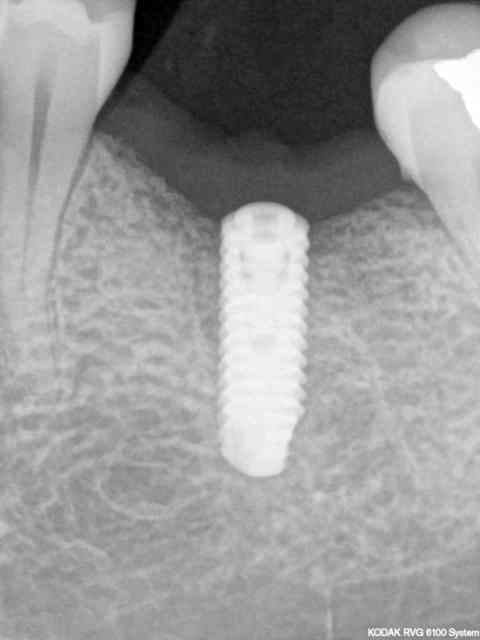

comme ce petit cas

la 2ème radio est prise 18 mois après la 1ère